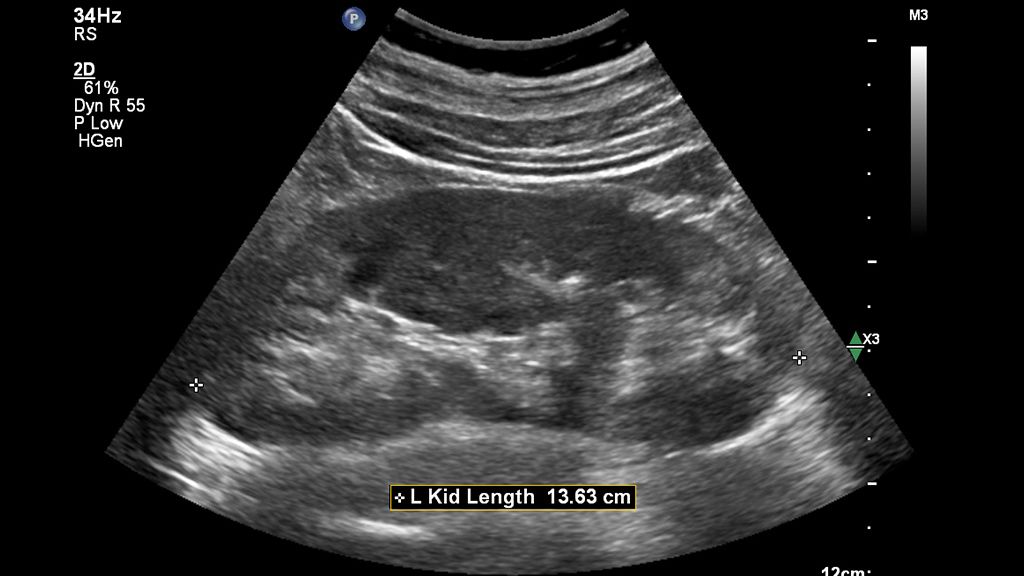

AI-driven Auto Measure Abdomen - Philips